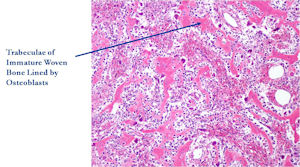

- They have a similar appearance microscopically as a conventional osteoblastoma except the osteoblasts are twice as large and have an epithelioid quality with abundant eosinophilic cytoplasm (Epithelioid Osteoblasts).

The differential between osteoid osteoma, conventional osteoblastoma and aggressive osteoblastoma is based on size and the presence of epithelioid osteoblasts. Can have epithelioid osteoblasts in osteoid osteoma and conventional osteoblastoma but they do not occur in cohesive sheets that fill intertrabecular spaces